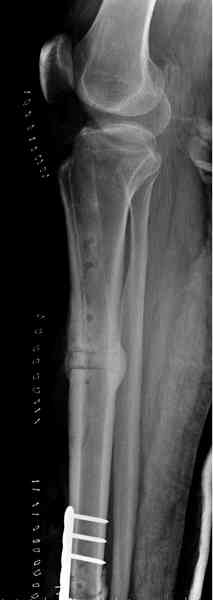

Недавно на нашей ежемесячной Morbidity&Mortality

conference мы разбирали похожий случай, ложный сустав большеберцовой кости после резекции опухоли.

К нашему онкологу-ортопеду обратился больной с жалобами на боли в голени, из рассказа - год назад была сделана биопсия большеберцовой кости, но название заболевания "не запомнил”.

Оперирован в военном госпитале с заменой сегмента

аллокостью большеберцовой кости и после демобилизации явился для постоянного наблюдения по месту жительства.

Наши имели проблему со сращением, пришлось им сделать динамизацию, дополнительную аутопластику.

Снимки представлены.